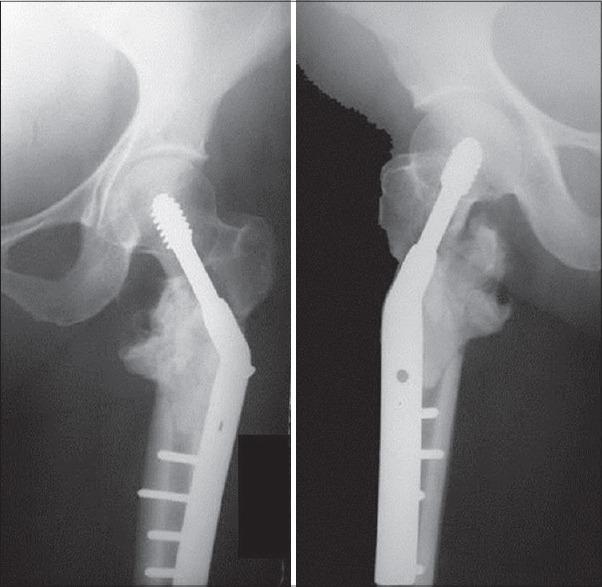

Skeletal metastasis is a common cause of severe morbidity, reduction in quality of life (QOL) and often early mortality. Its prevalence is rising due to a higher rate of diagnosis, better systemic treatment, longer lives with the disease and higher disease burden rate. As people with cancer live longer and with rising sensitivity of body imaging and surveillance, the incidence of pathological fracture, metastatic epidural cord compression is rising and constitutes a challenge for the orthopedic surgeon to maintain their QOL. Metastatic disease is no longer a death sentence condemning patients to "terminal care." In the era of multidisciplinary care and effective systemic targeted and nontargeted therapy, patient expectations of QOL, even during palliative end of care period is high. We lay emphasis on proving the diagnosis of metastasis by biopsy and histopathology and discuss imaging modalities to help estimate fracture risk and map disease extent. This article discusses at length the evidence and decision-making process of various modalities to treat skeletal metastasis. The modalities range from radiation including image-guided, stereotactic and whole body radiation, systemic targeted or hormonal therapy, spinal decompression with or without stabilization, extended curettage with stabilization, resection in select cases with megaprosthetic or biological reconstruction, percutaneous procedures using radio frequency ablation, cementoplasties and discusses the role of emerging modalities like high frequency ultrasound-guided ablation, cryotherapy and whole body radionuclide therapy. The focus lies on the role of multidisciplinary care, which considers complex decisions on patient centric prognosis, comorbidities, cost, feasibility and expectations in order to maximize outcomes on QOL issues.

骨转移是导致严重发病、生活质量(QOL)下降以及常出现早期死亡的常见原因。由于诊断率提高、全身治疗效果更好、患者带病生存时间延长以及疾病负担率上升,其患病率正在上升。随着癌症患者生存期延长以及身体成像和监测的敏感性提高,病理性骨折、转移性硬膜外脊髓压迫的发生率正在上升,这对骨科医生维持患者的生活质量构成了挑战。转移性疾病不再是宣判患者“临终关怀”的死刑判决。在多学科护理以及有效的全身靶向和非靶向治疗时代,即使在姑息性临终关怀阶段,患者对生活质量的期望也很高。我们强调通过活检和组织病理学来证实转移瘤的诊断,并讨论有助于评估骨折风险和描绘疾病范围的成像方式。本文详细讨论了治疗骨转移的各种方式的证据和决策过程。这些方式包括放疗,如影像引导放疗、立体定向放疗和全身放疗、全身靶向或激素治疗、有或无内固定的脊柱减压、扩大刮除术加内固定、在某些病例中进行假体或生物重建的切除术、使用射频消融、骨水泥成形术的经皮手术,并讨论了高频超声引导消融、冷冻疗法和全身放射性核素治疗等新兴方式的作用。重点在于多学科护理的作用,它考虑以患者为中心的预后、合并症、成本、可行性和期望等复杂决策,以最大限度地提高生活质量相关问题的治疗效果。